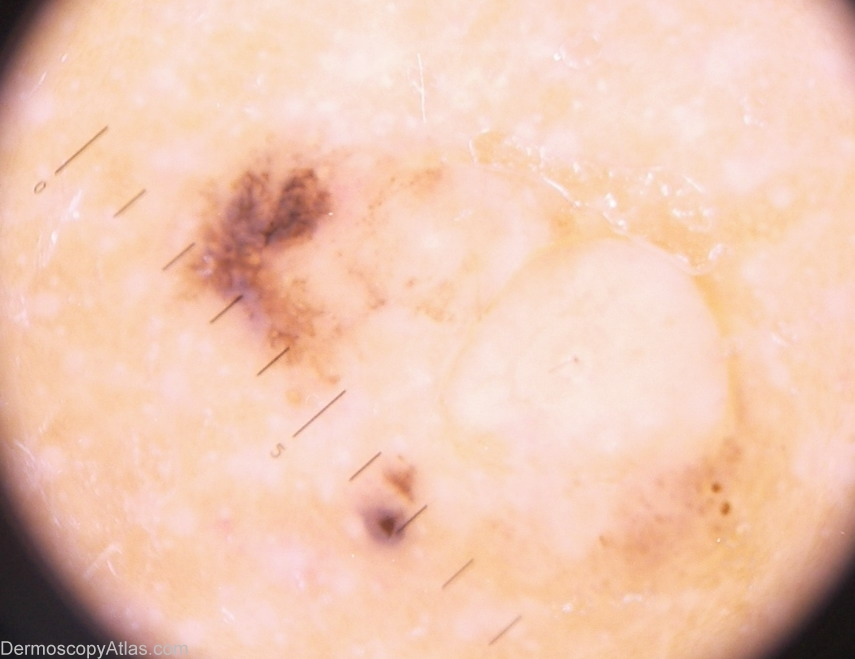

Diagnosis - Nevus recurrent

Diagnosis: Nevus recurrent